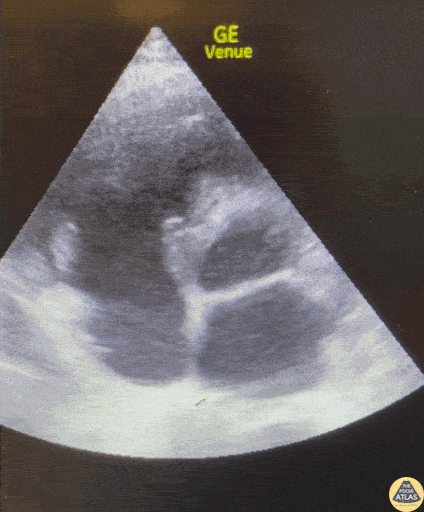

Valvulopathy - Tricuspid Valve Vegetation

50-60s F with PMH IVDU presents with chest pain, dyspnea, and fever. This POCUS image shows the parasternal short axis view at the level of the aortic valve, revealing a large vegetation on the tricuspid valve. Color doppler demonstrates tricuspid regurgitation. Daniel Fuchs, PGY3 Denver Health Residency in Emergency Medicine